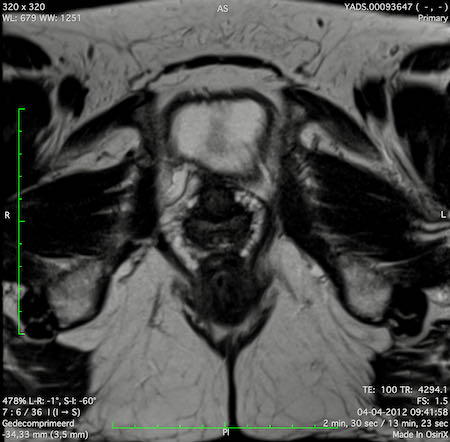

Hình ảnh

Các hình ảnh được cung cấp cho thấy ung thư biểu mô tế bào nhẫn với tình trạng dày lan tỏa thành trực tràng, hình ảnh bia bắn điển hình, và sự xâm lấn mỡ mạc treo trực tràng.